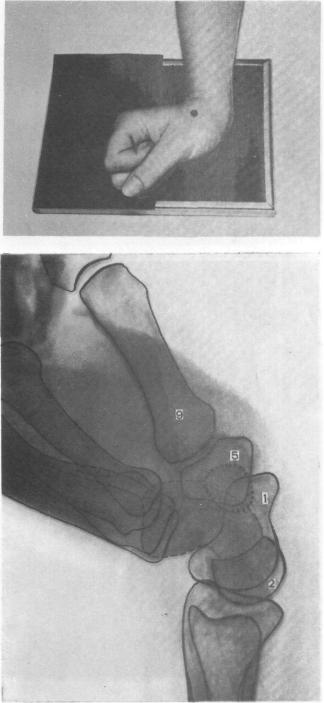

Подборка рентгеновских снимков лучезапястного сустава

Раздел: Объективный взгляд